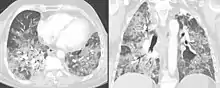

O diagnóstico é baseado na história de sintomas após a exposição ao alérgeno e em testes clínicos. Exames de sangue indicam sinais de inflamação pouco específicos, a radiografia de tórax revela áreas de opacidade difusa, pode haver edema e fibrose, e testes de função pulmonar revelam doença pulmonar restritiva.[6]